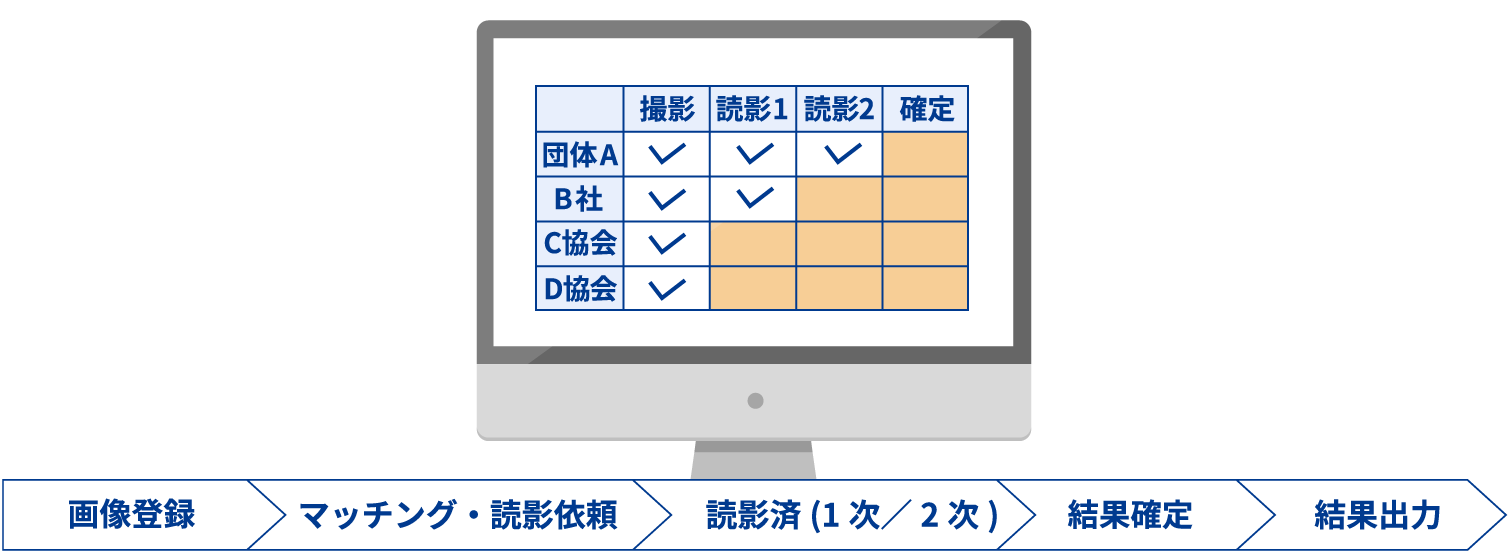

画像登録から結果確定までの健診読影業務を

トータルサポート!

事務業務の人的ミス・負担を軽減したい!

- 画像登録から結果出力までの進捗状況を、一覧画面で簡単に確認

読影の進捗状況を一覧画面で管理

健診種別を細かく設定して管理可能